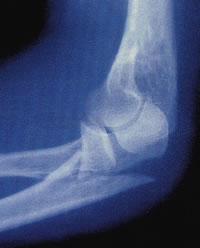

Az osteoporosis oka a népesség elöregedése és olyan civilizációs ártalmak, mint a minőségileg nem megfelelő étkezés, továbbá a mozgáshiány sorolja dr. Bálint Géza, a csont és ízület évtizedének hazai koordinátora. A csontritkulást azért hívják néma járványnak, mert amíg nincs törés, nincs gond. Különösen a csukló, a csípőtáj és a csigolyák sérülékenyek. A törések megelőzése nemcsak azért lenne fontos, mert a kezelésük óriási költségekkel jár, hanem amellett, hogy rontja a beteg életminőségét, jelentősen megnő egy újabb csonttörés kockázata. 1990-ben a csípőtáji törések száma a világon egymillió-hétszázezer volt, a becslések szerint ez a szám 2050-ig több mint hatmillióra emelkedik.